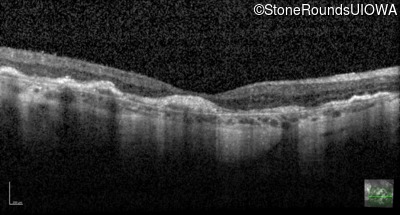

Optical Coherence Tomography - Right - 20/160 -2

Exemplar / OCT Stack

OCT Stack